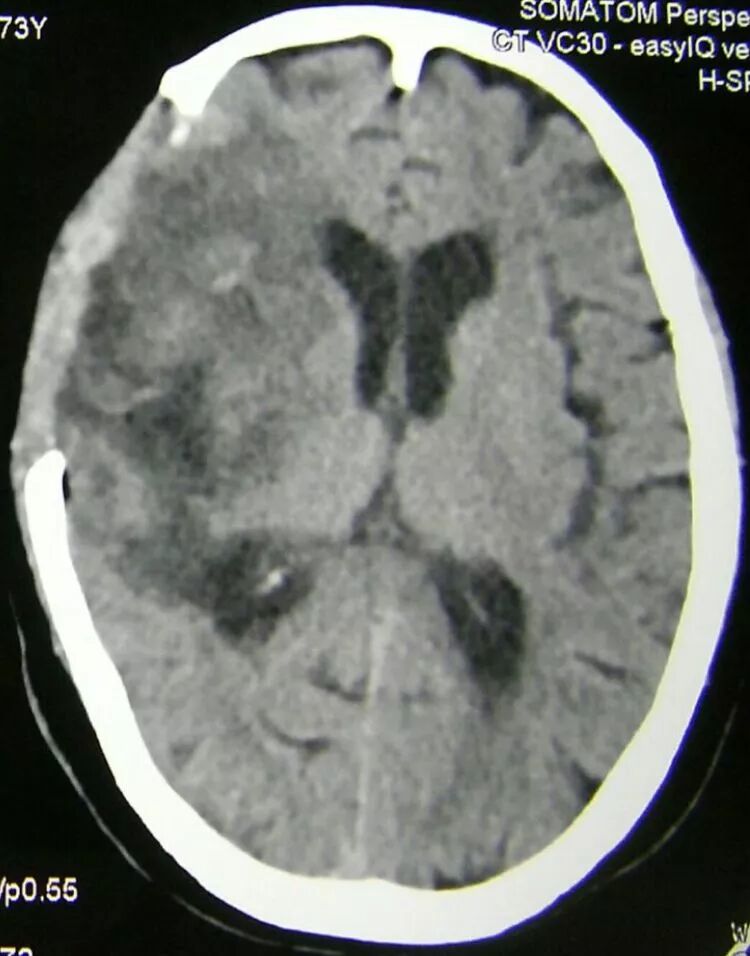

术后2周CT复查,水肿基本消退,中线良好,脑池清晰,脑室无扩张。